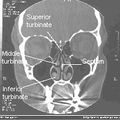

يعتبر الجدار الوحشي أكثر جدران جوف الأنف تعقيداً؛ إذ يساهم في تركيبه كل من العظم الأنفي والغربالي والدمعي والفكي العلوي والصفيحة العمودية للعظم الحنكي والصفيحة الجناحية الأنسية للعظم الوتدي. يتميز الجدار الوحشي ببروز ثلاث تراكيب عظمية تتوضع فوق بعضها تدعى المحارات الأنفية.[1][6] كما يتميز الجدار الوحشي بوجود ارتفاع دائري ينتج عن بروز الخلايا الغربالية المتوسطة نحو الأنسي يدعى الفقاعة الغربالية، وإلى الأسفل والأمام من هذه الفقاعة يوجد ثلم متقوس يدعى الفرجة الهلالية.[6]

يقسم جوف الأنف بواسطة حاجز الأنف إلى قسمين أيمن وأيسر، ويقسم كل منهما بواسطة المحارات الأنفية الثلاثة إلى أربع فسحات هي من الأعلى للأسفل:

- الردب الوتدي الغربالي: يقع فوق المحارة الأنفية العلوية وخلفها.

- الصماخ الأنفي العلوي: يقع تحت المحارة العلوية ووحشيها.

- الصماخ الأنفي الأوسط: يقع تحت المحارة الأنفية الوسطى ووحشيها.

- الصماخ الأنفي السفلي: يقع تحت المحارة الأنفية السفلية ووحشيها.[1]